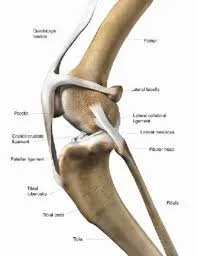

ligaments of dogs knee

One of the most common orthopedic problems in dogs is a cranial cruciate ligament tear, often referred to as an ACL tear.

The cranial cruciate ligament stabilizes the knee joint. When this ligament tears, the joint becomes unstable and painful.